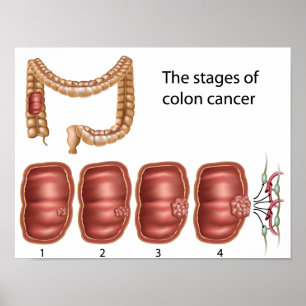

Poster sur la progression du cancer du côlon

Prix52,95 €